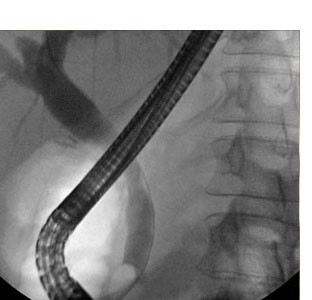

Altering Clinical Care with Cholangioscopy

Direct visualization during an ERCP may result in a faster more definitive diagnosis of pancreatic and biliary cancers.1,3 When used in conjunction with laser or EHL, cholangloscopy efficiently treats biliary stones potentially reducing the need for reintervention.1,3

Images of benign and malignant conditions in the biliary and pancreatic ducts

Cholangioscopy Image Reference Guide

Learn more about the characteristics of various biliary and pancreatic diseases and conditions using the SpyGlass™ DS System, from views of normal ducts to benign and malignant conditions. You can also submit your own procedural images for consideration.